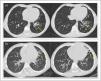

En ninguno se sospechó aspiración de CE por ausencia de episodio asfíctico, produciendo el retraso diagnóstico y la aparición de bronquiectasias, aún presentes 5 años después (fig. 3).